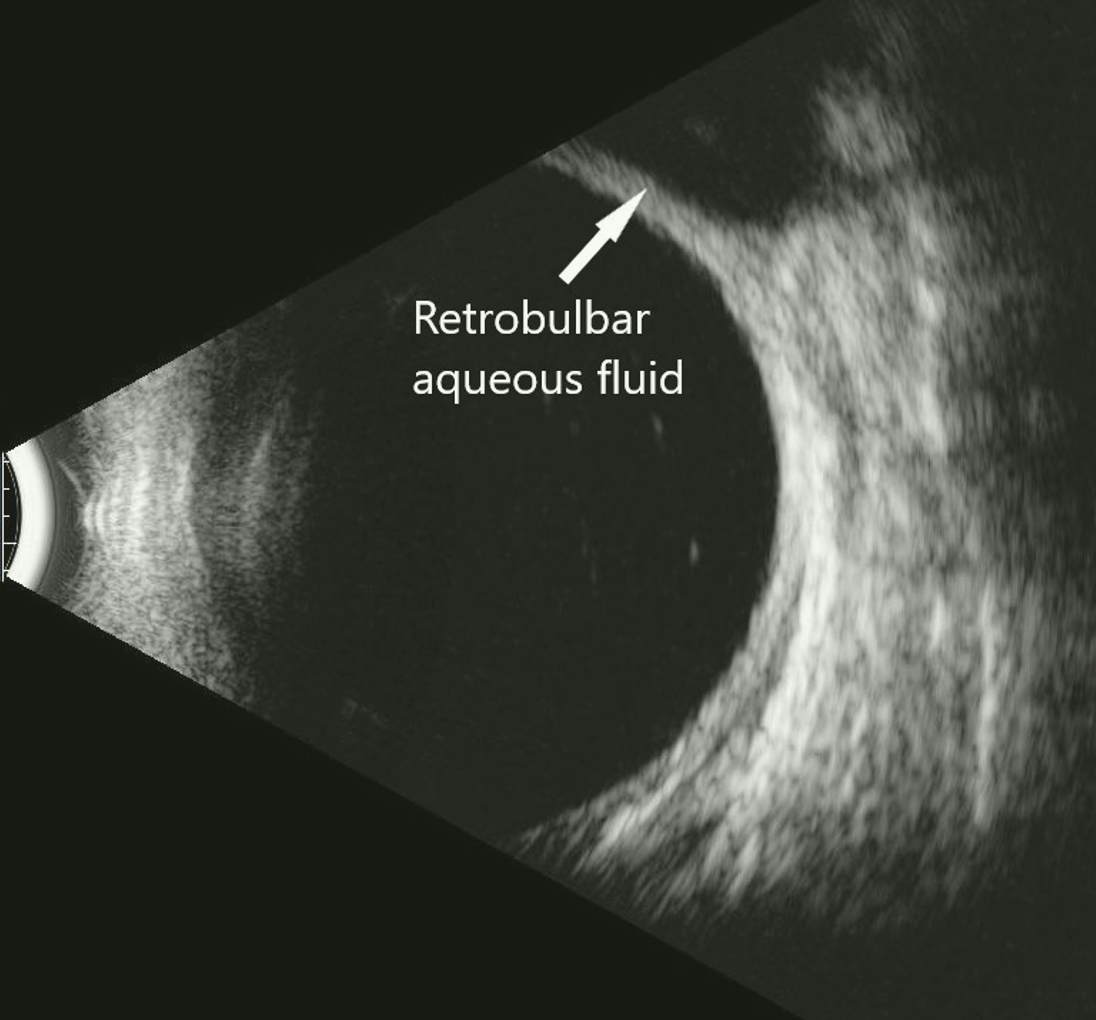

On post-op day 1, the patient’s ocular medications were prednisolone acetate OD QID, ofloxacin OD QID, brimonidine 0.2% OS BID, dorzolamide 2% OS BID, and latanoprost 0.005% OS QHS. The vision was HM in the right eye and 20/25 in the left eye. The IOPs were 3 mmHg OD and 15 mmHg OS. The anterior chamber was shallow with peripheral choroidal effusions in the right eye. At post-op week 1, the BCVA was HM OD and 20/25 OS, while the IOP was 5 mmHg OD and 14 mmHg OS with decreased shallowing of the anterior chamber in the right eye. The ofloxacin OD was discontinued at this time. At the post-op 1 month visit, the vision improved in the right eye to 20/200 and the IOP increased to 11 mmHg in the right eye and 16 mmHg in the left eye. At the 4-month post-op visit, the vision improved to the baseline of 20/70 OD and the IOP was 8 mmHg OD and 16 mmHg OS. The VF MD was -33.6 OD and -.12 OS. At post-op month 12, the vision was stable at 20/80 OD and the IOP was 7 mmHg OD and 16 mmHg OS. The patient was on no glaucoma medications for her right eye (Figure 4, MRI of orbit right eye; Figure 5, B-scan of aqueous in the right eye).

Figure 5

B-scan of aqueous in retrobulbar space.